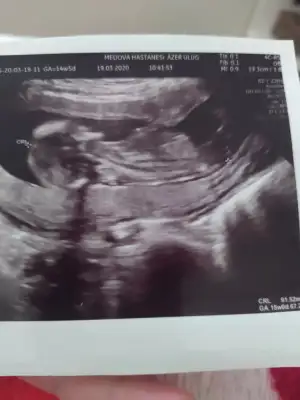

Merhabalar, ctesi ikili test icin gittim 11+6 idim. Suana kadar hep haftayla uyumlu giderdi sat. Ama bu sefer 12+6 cıktım. Yine de cinsiyet yorumlar mısınız? Gec mi kaldım? Bir de doktor tahminini söyledi ama emin değil. Kafanız karışmasın diye en son söyleyeceğim.

Bir de bunu verdi doktor. Sanırım bacak arası ve kenardakiler de bacakları burada. 11+6 idim.